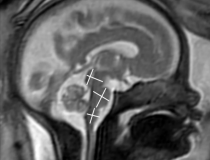

This photo gallery shows the variety of radiological presentations of COVID-19 (SARS-CoV-2) in medical imaging, including computed tomography (CT), radiograph X-rays, ultrasound, echocardiograms and magnetic resonance imaging (MRI). The radiology images show examples of typical COVID pneumonia in the lungs and the numerous complications the virus causes in the body in multiple organs, including the brain, kidneys, heart, abdomen and vascular system.